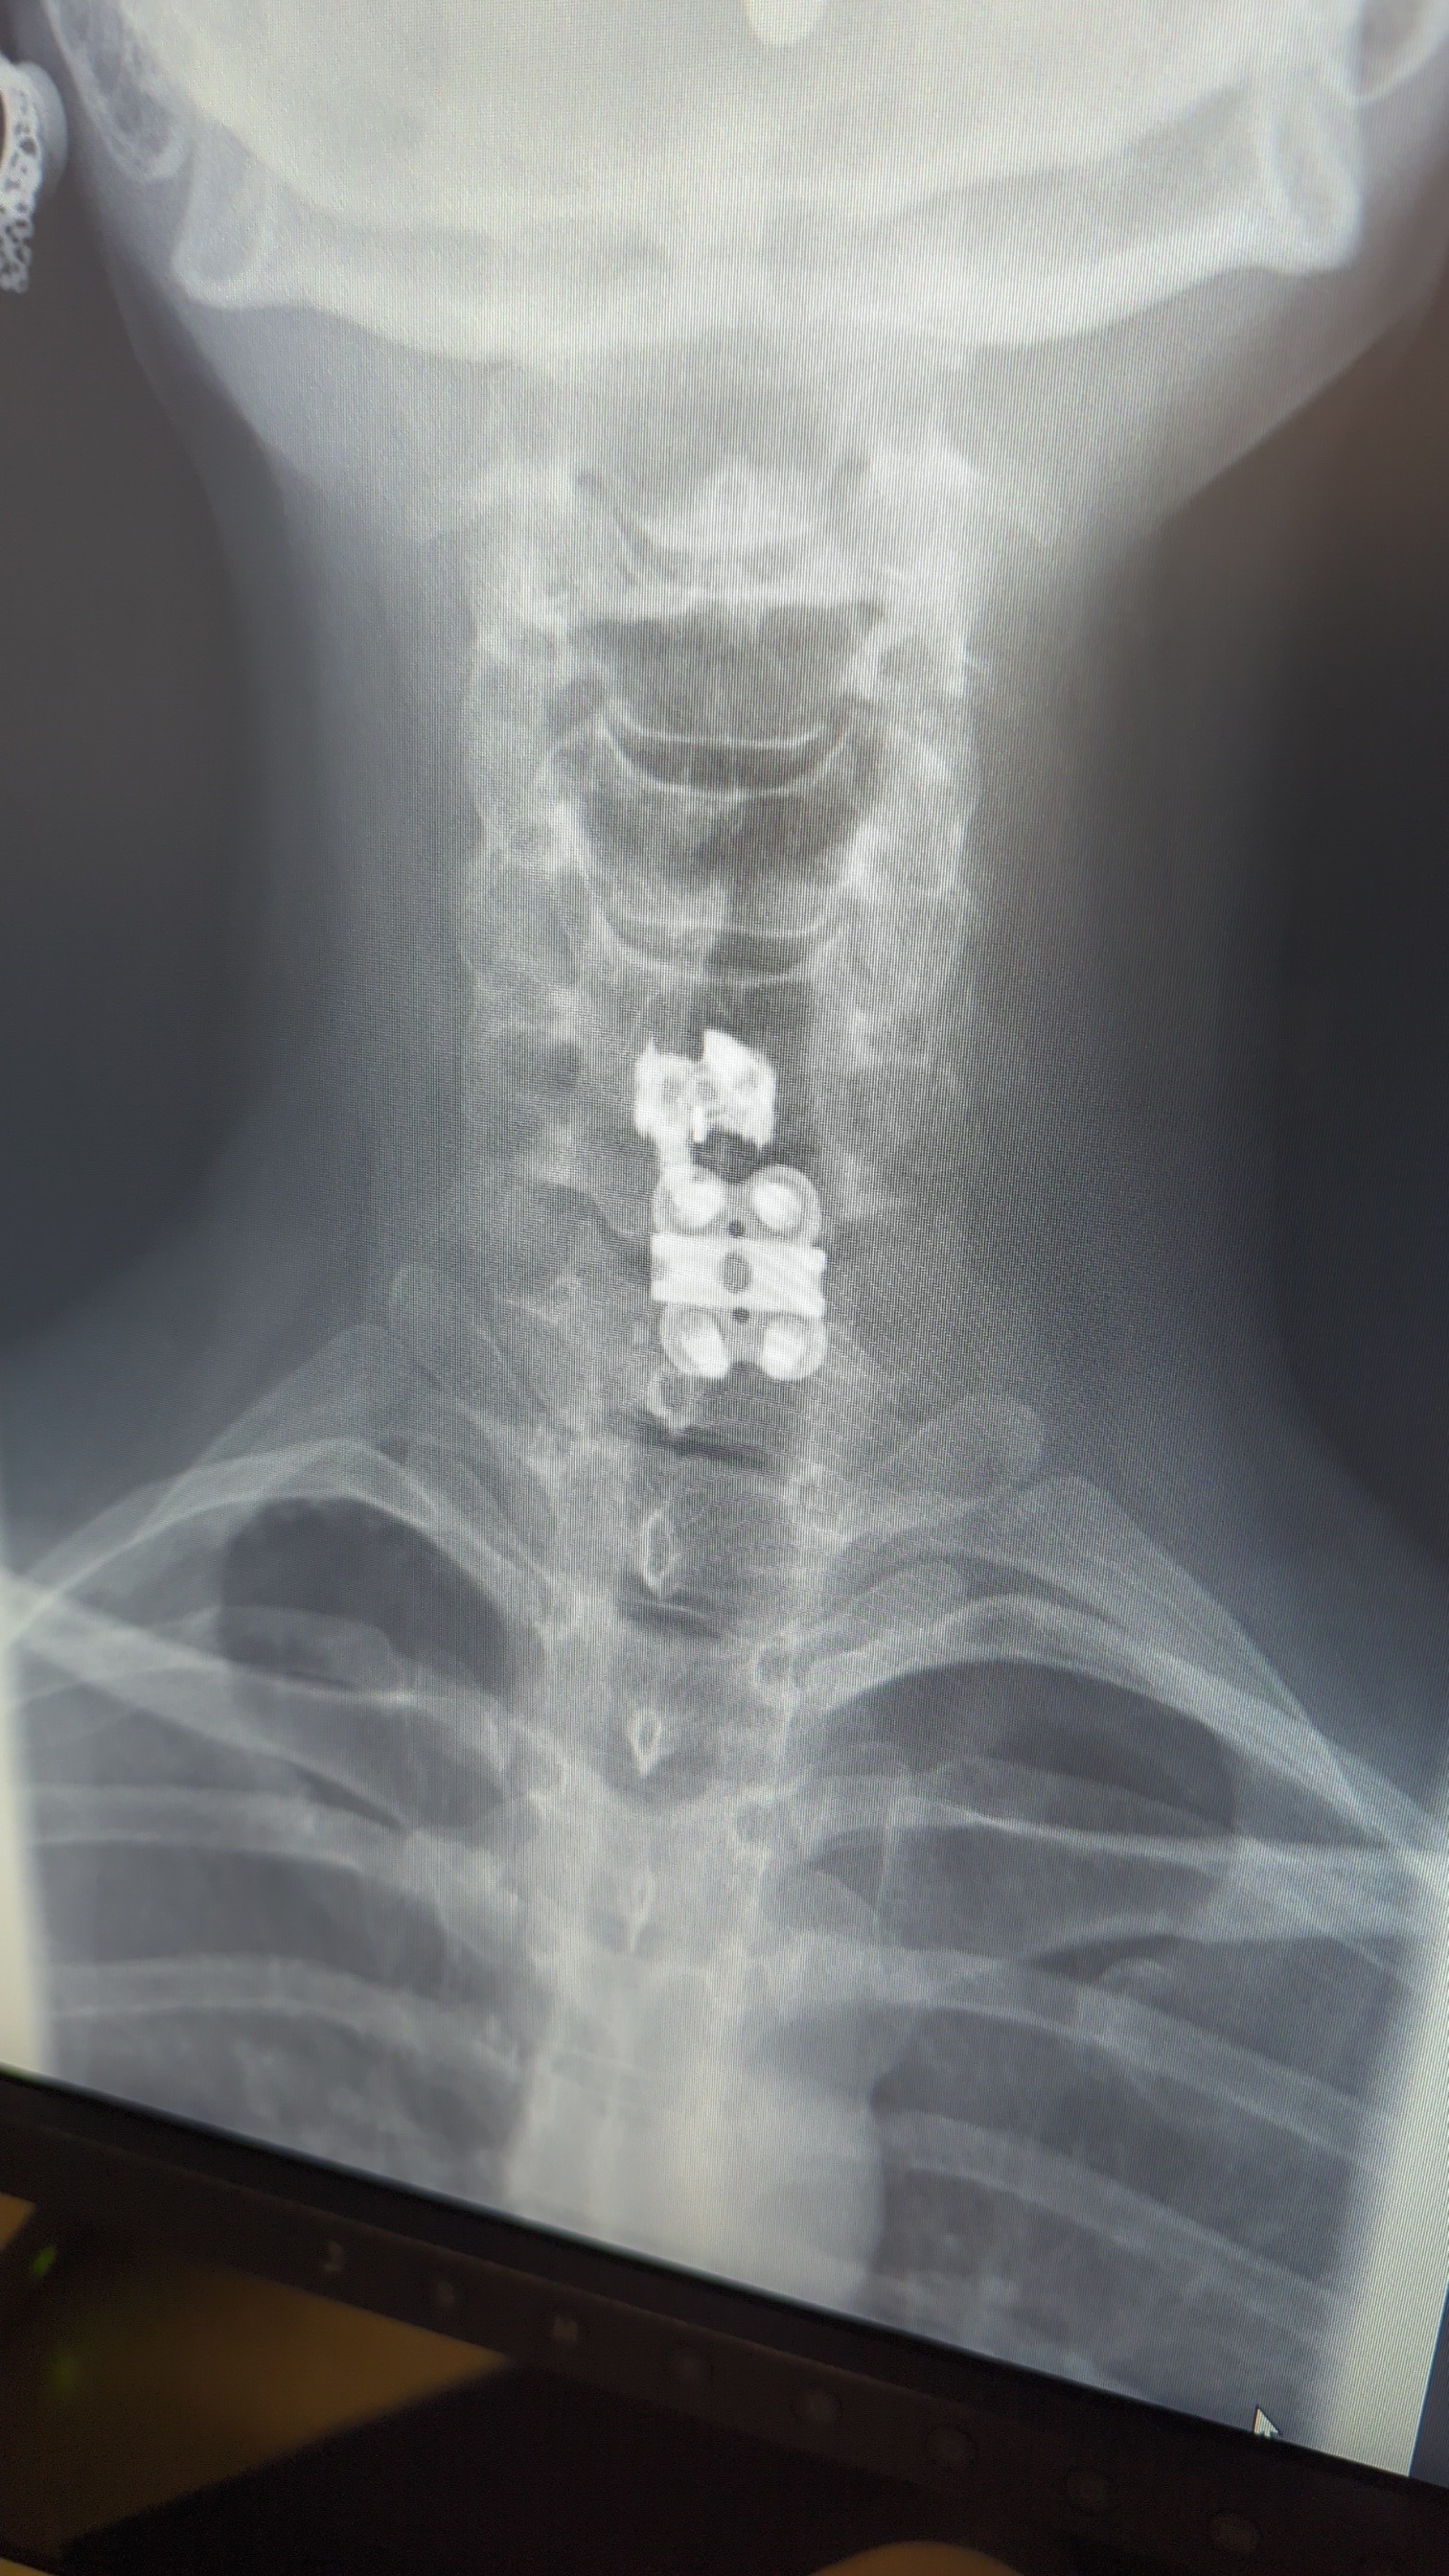

Hi, my name is Heather and I'm a single Mom of two beautiful teenage girls. We moved away from FL almost 2 years ago, and my health has taken a dramatic turn for the worst. Drs are telling me to get home to family and friends as soon as I can. Drs are worried the longer I take to get home the harder it may be for me to get there. 2 neck surgeries this year, 4 MRIs in the past 3 months, CT's, X-rays. All to determine I have chiari malformation and a mass that was found behind my throat and in front of my cervical spine. It's progressing fast. First spotted in May 2mm protruded and now it's measuring at 5 mid July. My balance has been compromised, my speech has been affected, my kids are having to help me stay standing or are lifting for me. Me trying to get home to FL will help me because that's where my mom and sister is,My friends, all who I havent seen in a couple years now. Knowing my health has taken a turn for the worst makes me know I do need help. And all of that is available for me in FL. I know everyone is hurting right now. Please just help us get home. Anything helps more than nothing. If you can't spare anything please just share so my story can go out.